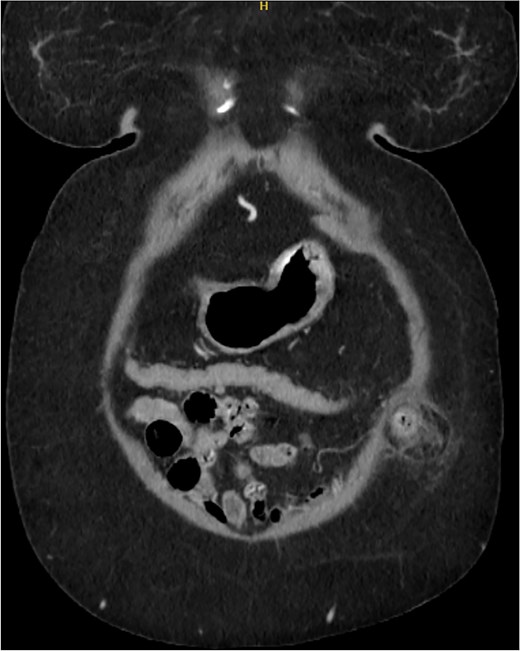

A 76-year-old female with a medical history of type 2 diabetes mellitus (controlled with oral medications), hypertension (on two medications), hyperlipidemia (on atorvastatin), and recently diagnosed Alzheimer’s disease (started on memantine) presented to the emergency department with severe left-sided abdominal pain of 2 days’ duration. The pain began gradually but worsened significantly in the last few hours. It was associated with a bulging mass in the abdomen that was tender and painful to touch. The patient reported that the swelling had been present for 2 years, intermittently reducible with minimal exertion. However, since the previous day, it had become irreducible and increasingly painful, particularly after a failed attempt to reduce it manually at home. She also admitted to chronic constipation for years, usually treated with oral laxatives, though she had not been compliant with them recently. Her surgical history included a laparoscopic cholecystectomy combined with paraumbilical hernia repair using mesh 3 years ago. Upon examination by the on-call surgical team, the patient was afebrile with stable vital signs. Her abdomen was distended, and a 7 × 7 cm irreducible, tender mass was noted over the left side. An urgent computed tomography (CT) scan of the abdomen and pelvis with intravenous and oral contrast revealed a left lateral ventral abdominal hernia traversing the left lateral oblique muscles. The hernia sac contained omental fat and an inflamed diverticulum of the transverse colon, with surrounding inflammatory changes. The defect measured 1.4 × 1 cm, and the hernia sac measured 6.7 × 4.2 × 4 cm. No free fluid, fluid collections, or pneumoperitoneum were identified (Figs 1–3).

Coronal section of CT abdomen and pelvis showing the ventral hernia.